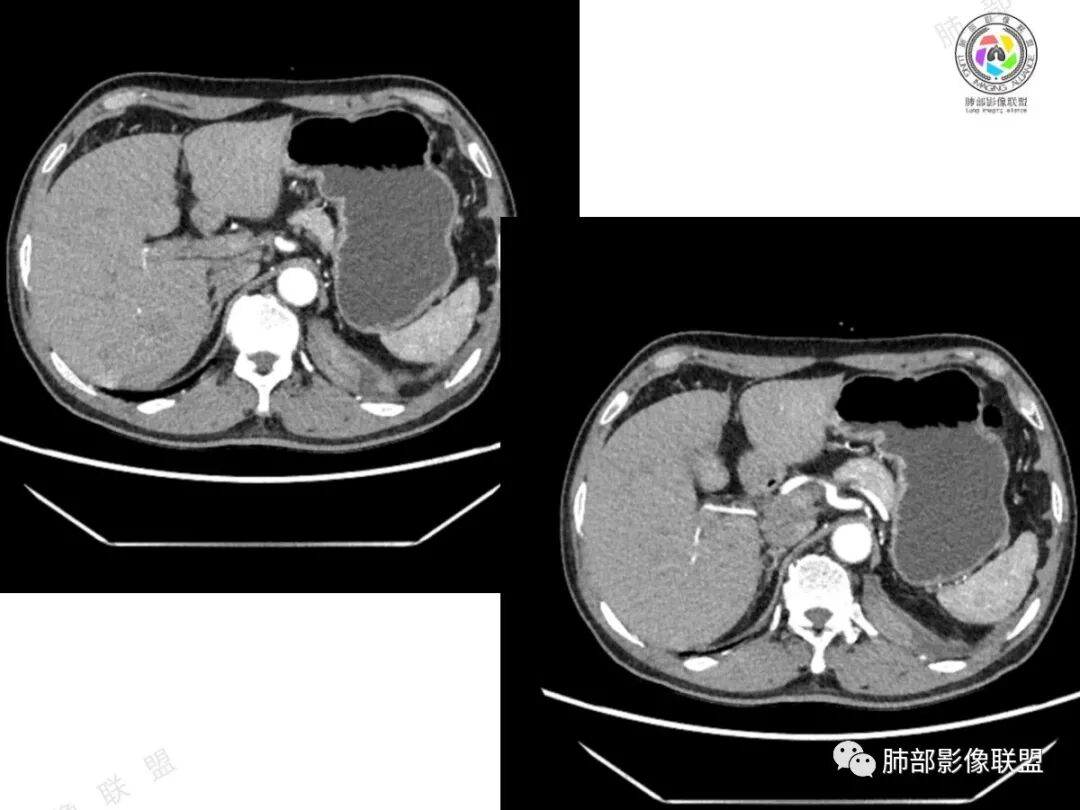

2、影像所见:左侧纵隔紧贴心包铸型生长巨大混杂密度肿块,边界清楚,临近结构受推挤移位,无明显外侵征象。肿块自主动脉弓旁一直顺延到至膈顶,呈“垂乳征”。病灶脂肪成分居多,斑片状、结节状及团块状实性密度成分散落其中,呈地图样分布,实性成分偶见低密度线样分隔,未见明确钙化影。增强扫描实性成分呈延迟明显强化,并见强化血管影。纵隔内有肿大淋巴结,未见胸腔积液,肺内及胸膜未见转移性病灶。

3、影像诊断:脂肪肉瘤?胸腺脂肪瘤?畸胎瘤?胸腺瘤?

①脂肪肉瘤:本例含较多脂肪组织,需考虑分化成熟型脂肪肉瘤(高分化型)的可能,其好发于前中纵隔的下部及心膈角区,肿块常大,偏于一侧,可有分叶,包膜可完整,与周围组织器官界限清楚。以脂肪密度为主的肿块,增强后仅见间隔或实性部分轻微强化。而本例实性成分过多,且实性病灶强化较明显,与高分化型脂肪肉瘤表现矛盾。

②胸腺脂肪瘤:好发于前下纵隔心膈角区,肿块一般较大,多见于40岁以下年龄患者,其内可见条状或片絮状胸腺组织,一般无周围侵犯。本例实性成分多、体积大,年龄较大,与胸腺脂肪瘤存在较多冲突。